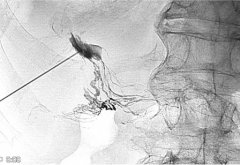

经肠系膜(淋巴管)栓塞 Transmesenteric embolization J Vasc Interv Radiol 2018;29(9):12901292...